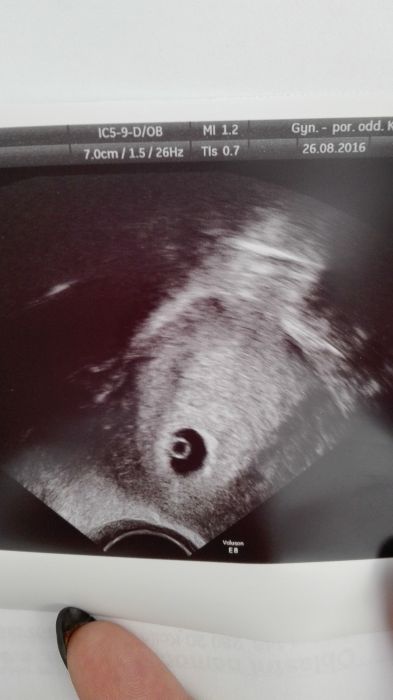

Ahoj holky,prave jsem dorazila domu a vse je kde ma. Zatim jeste neni videt srdicko,ale to pry jeste brzo. Jsem 5+3tt. Tak jsem si musela nechat udelat fotecku aspon naseho flicku.

[931660] jde vidět krásný zloutkovy váček :) příště už bude určitě i flíček se srdíčkem ;) kdy máš jít já kontrolu? A dekuju :)